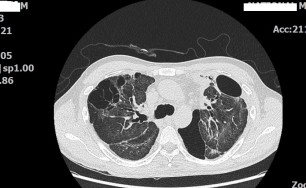

숨케어한의원에서는 전화예약을 받고 있습니다. 내원시 엑스레이, CT사진, 폐기능검사지를 가지고 오시면 자세한 상담이 가능합니다.